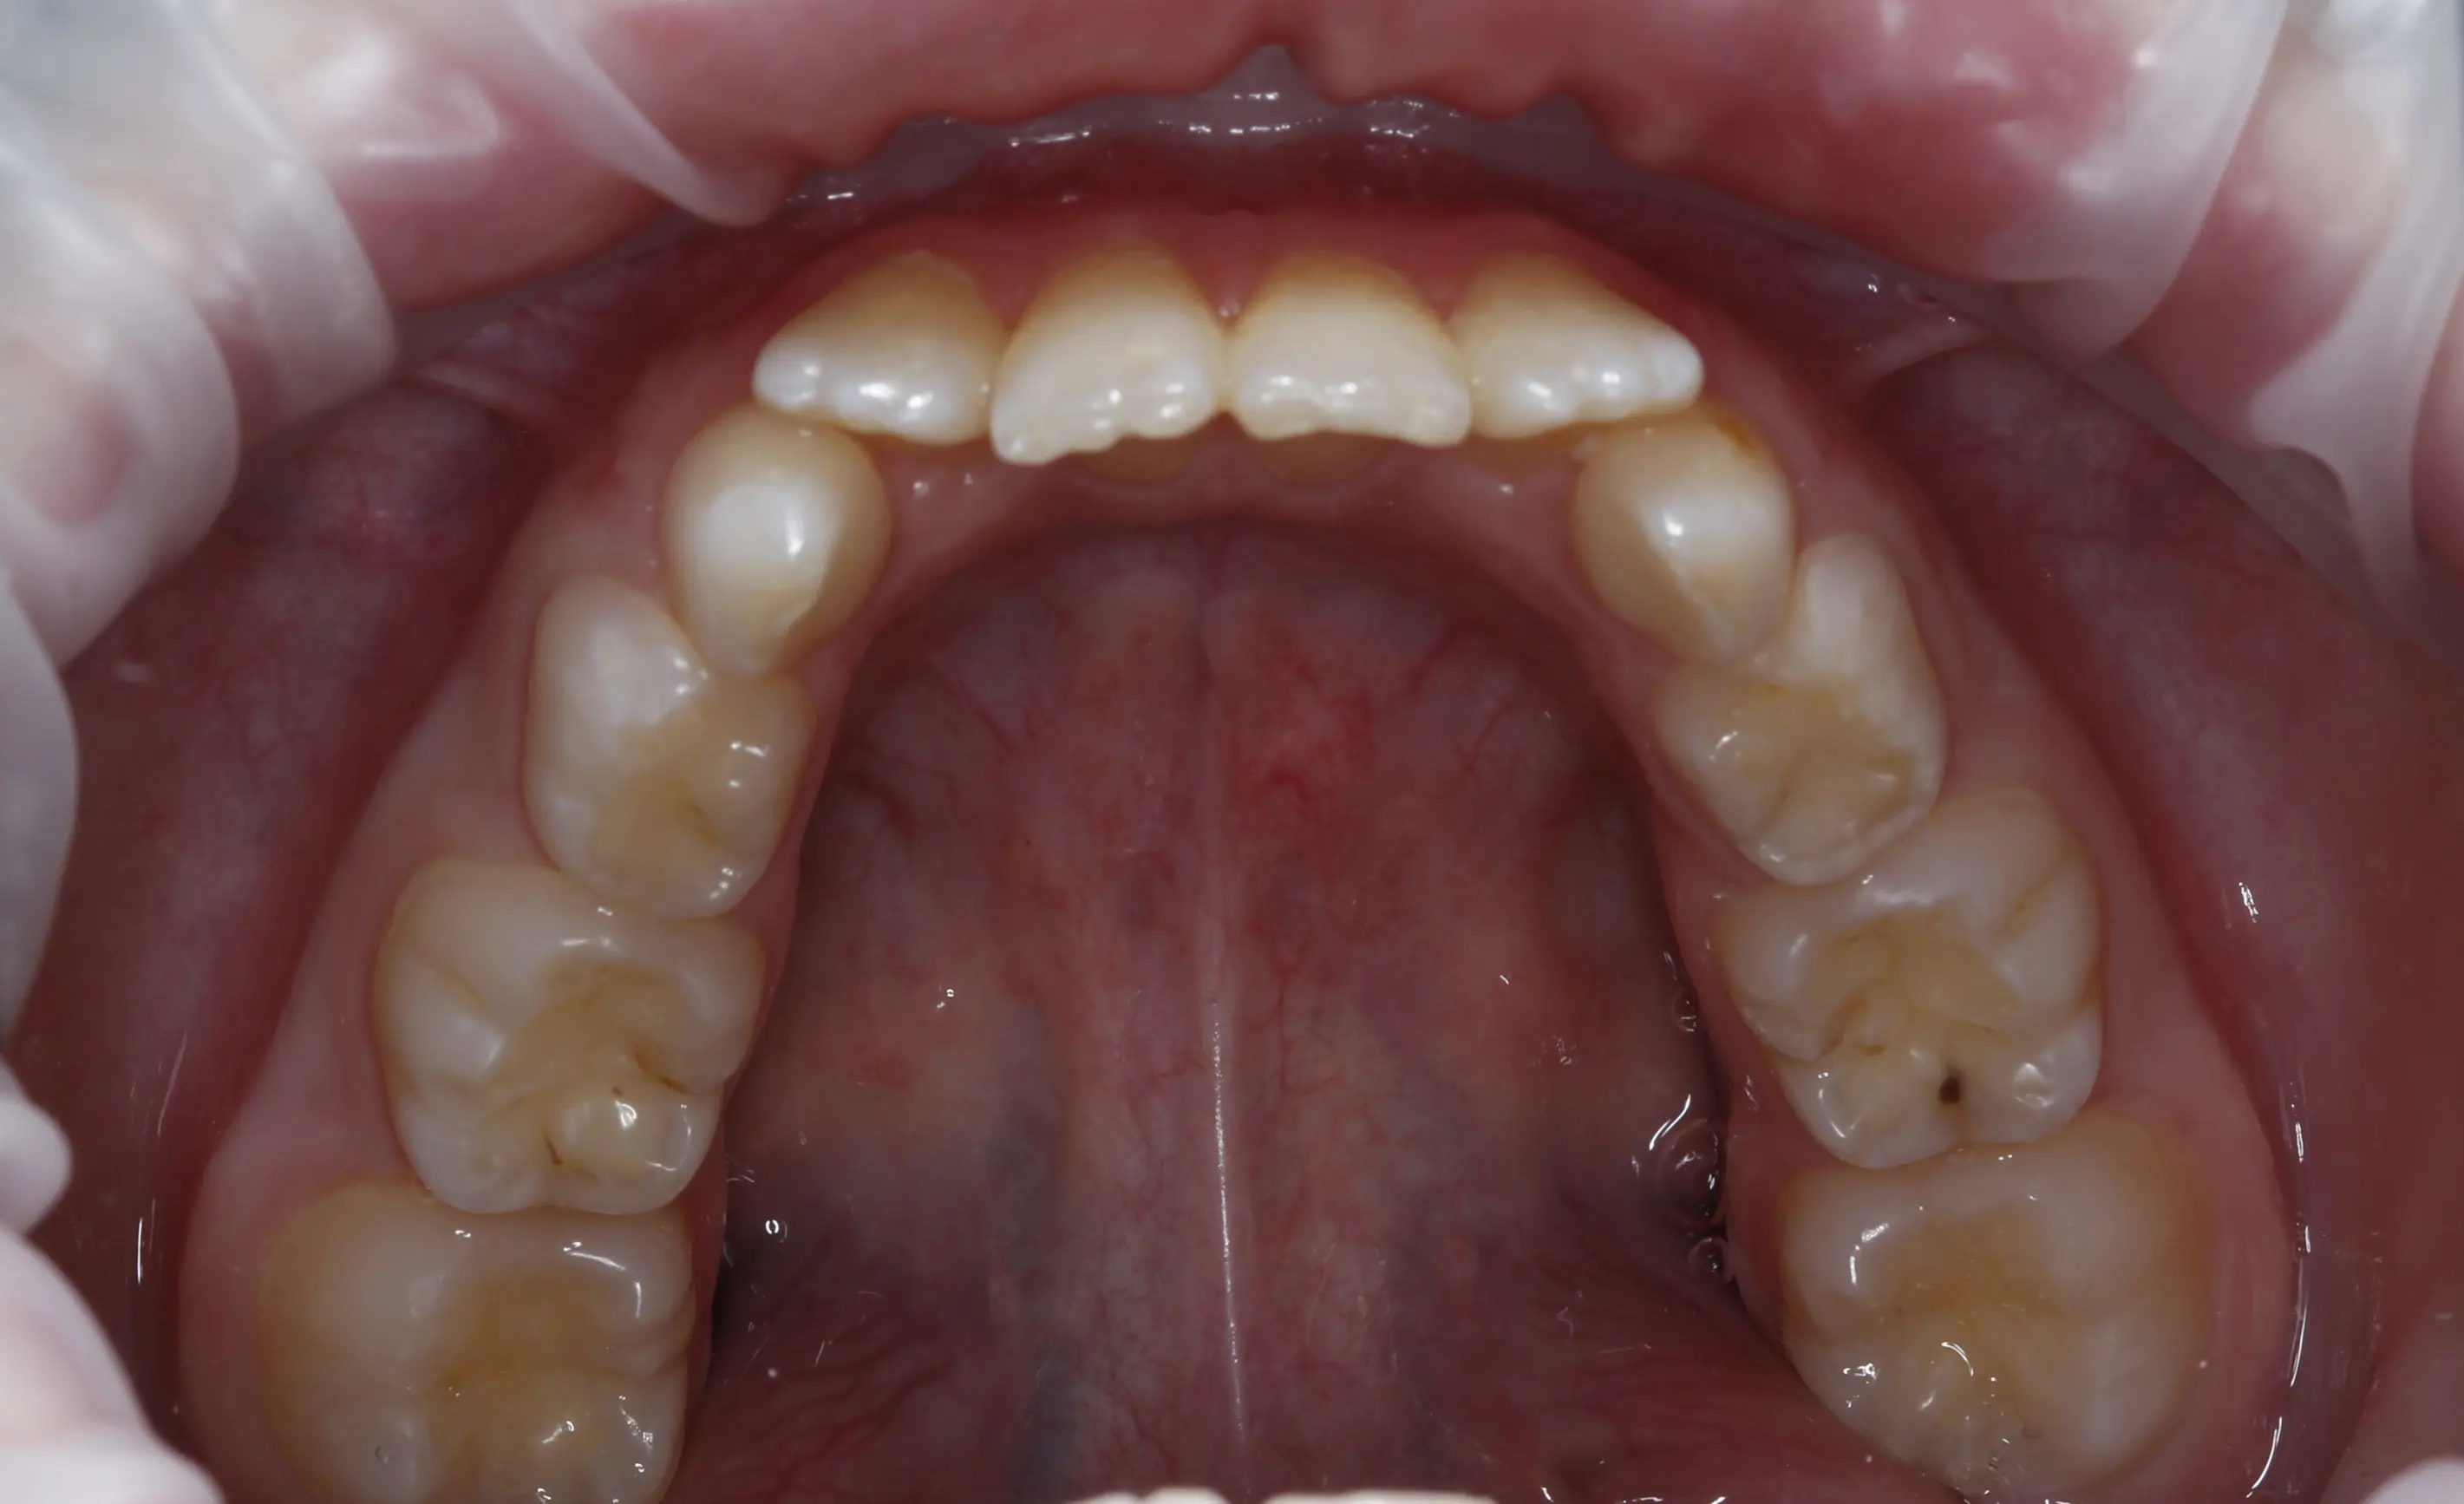

після

Результат - відновлений баланс у фронтальній ділянці, правильне положення зубів і передумови для гармонійного розвитку прикусу